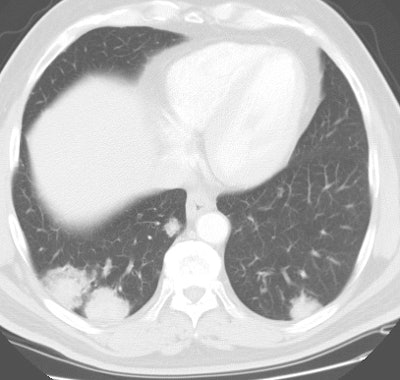

Bronchoalveolar cell carcinoma presenting at multiple poorly marginated lung nodules- some of which appear cavitary. The findings mimic a pulmonary infectious process. |